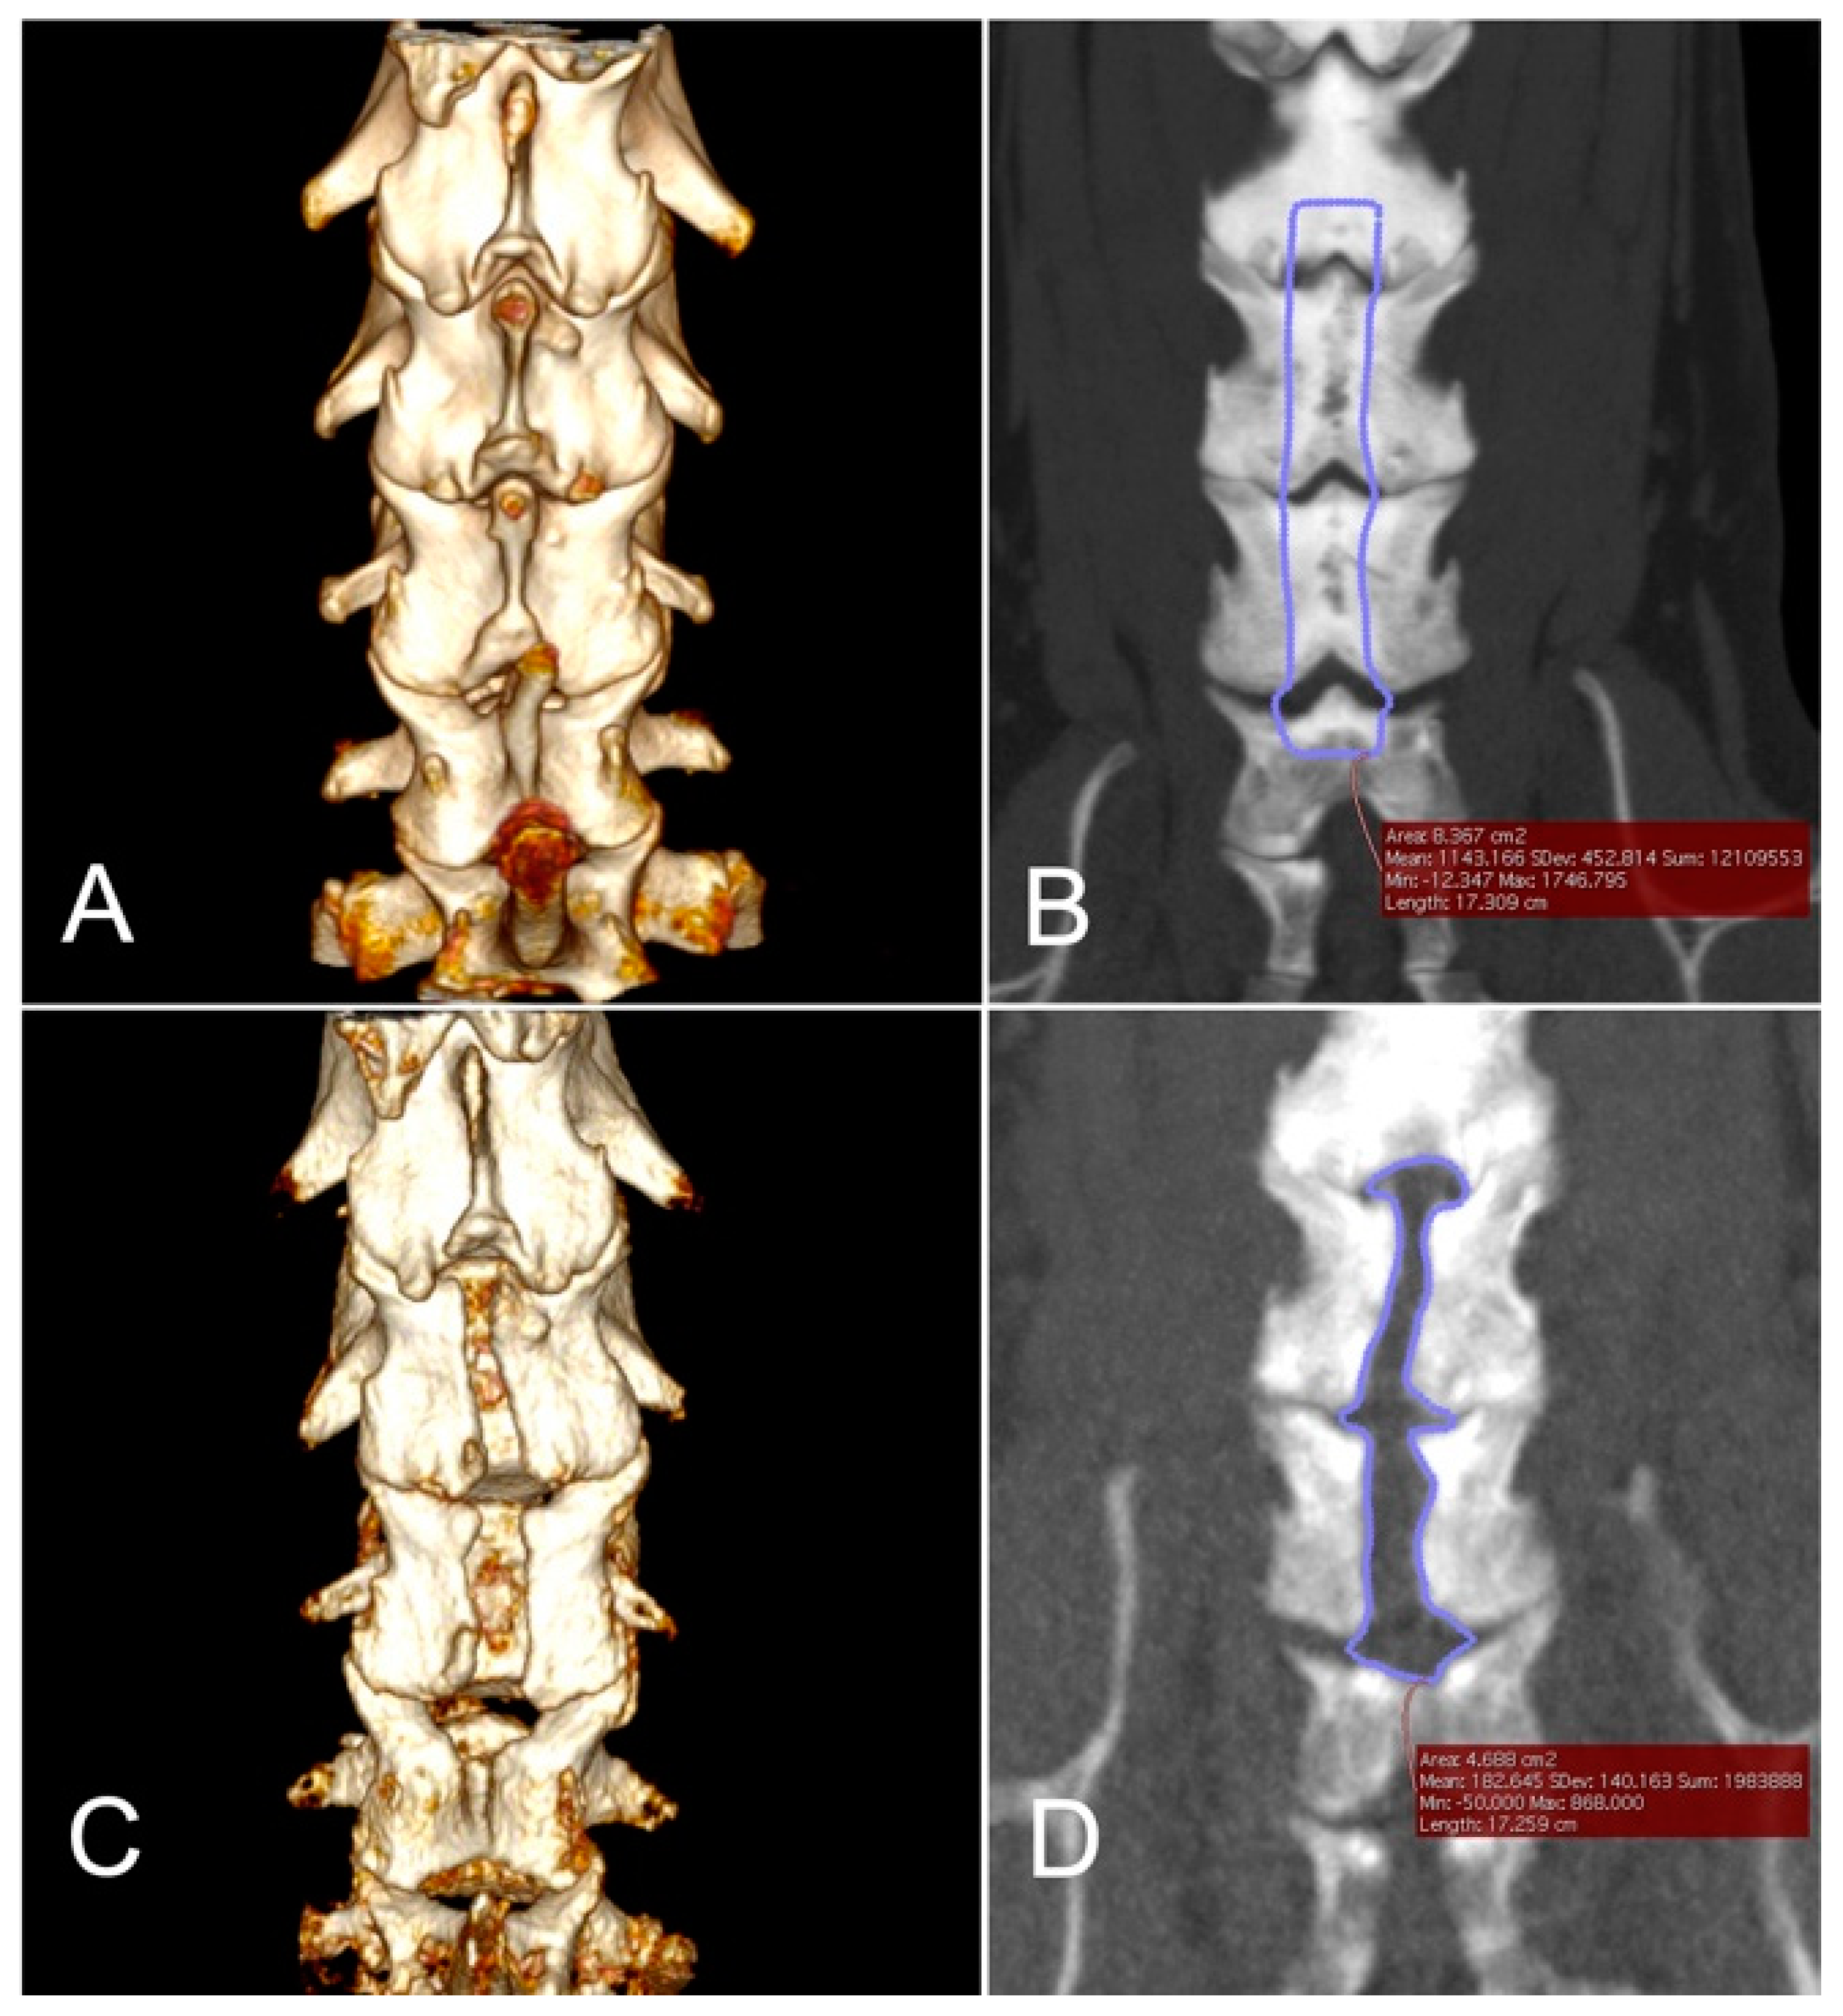

2.6. Imaging Analyses

3.4. Morphometric Analyses

| 4 | C4, C5, C6, C7 | 324 * | 19 × 70 | NA | 8.367 | 4.688 | 56.03 |